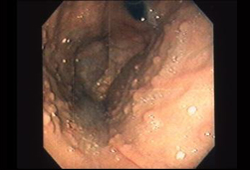

Key diagnostic factors

- family history of FAP/attenuated FAP

- teenager

- onset of colorectal cancer in middle age

- constipation/diarrhoea

- haematochezia